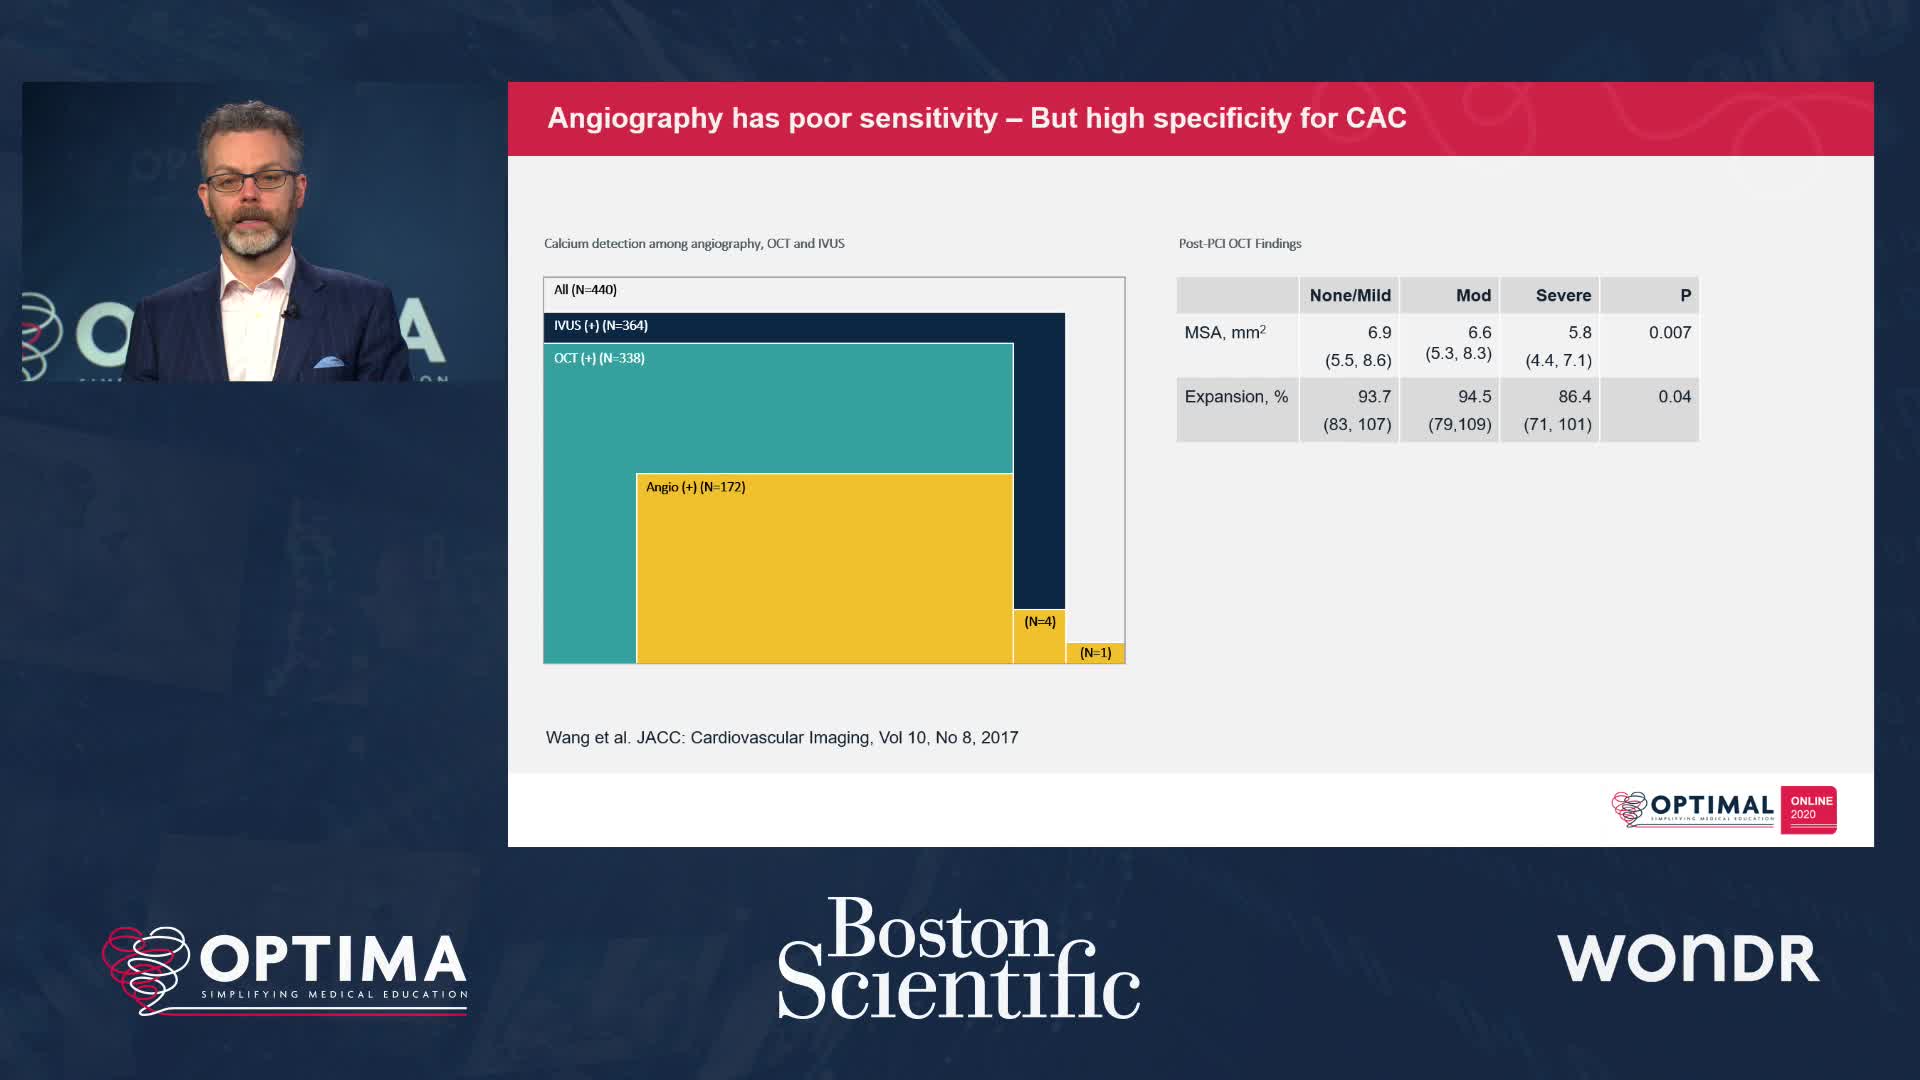

Session 2: Coronary calcium – too hard to crack?

Treatment of coronary arterial calcium (CAC) has being redefined. We explore the interaction between CAC and patient...